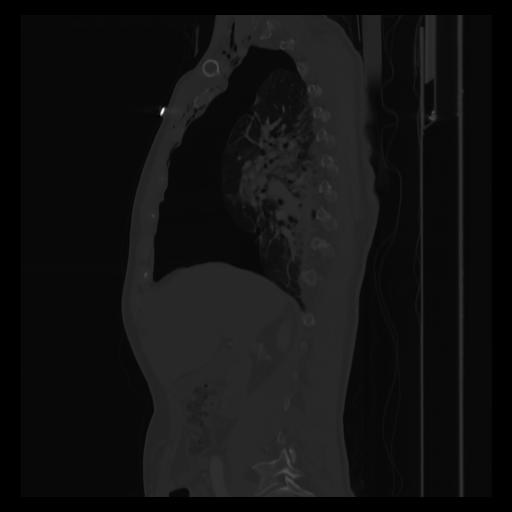

30 CUERPO,CE,Sagittal,3.000,CUERPO,Sagittal,